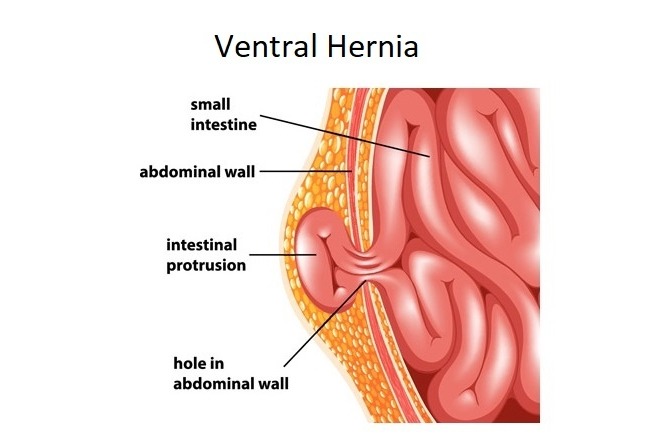

Back in January 2004 I was diagnosed with a large Hiatal Hernia with extreme GERD I then had a laparoscopic Nissen Fundoplication to try and repair this. After the surgery I still felt the sliding up and down motion and found it hard to breathe. I then went back to the surgeon that repaired it and he said it was fixed. I knew It wasn’t right, so I went and searched for other doctors. I found a doctor out of state and he also said I did not have a Hiatal Hernia. I told him I had “A knocking below my sternum” and so he removed half of it this left a Ventral and Incisional Hernia and I still felt an up and down motion leaving me extremely short of breath. I then found another G.I. doctor who found the problem. I had a large Sliding Hiatal Hernia at the 35cm at the E.G. Junction with the Nissen intact. He referred me to a surgeon who confirmed a Ventra Hernia with many adhesions. He never repaired the Hiatal Hernia, but the mesh and adhesion removal helped, and I’ve been functional for 14 years. However, I started working at a wholesale club where I had to twist and bend while lifting heavy things. At the same time, I contracted Bronchitis and I coughed a lot and gagged. I felt something pop and then all my symptoms began. I was able to get a surgeon right a way who did a CAT Scan. The CAT Scan showed a large Ventral and Abdominal Wall Hernia. My stomach, liver, and intestines were protruding outside my Ventral and abdominal wall. The next day they performed emergency surgery. I had my original paperwork from 2004 but they refused to see it. They opened me up and put mesh in the Ventral and Abdominal Wall. This seem to only make my breathing and sliding of my Hiatal Hernia worse. They said I did not have/ did not see a Hiatal Hernia. This seems impossible because they don’t just magically disappear. A week and a half post-surgery every time I breathe or talk it feels like my stomach is moving up and down and slamming into the mesh they placed in the Ventral area. I am unable to eat, sleep, or breath very well. I do not have any quality of life because I am too out of breath and this big bulge comes up when I breathe. I have told them of my symptoms, but the surgeon says he will not do anything until the surgery heals. I feel helpless and feel with every breathe I am going to die. I can’t eat so I am very weak. I need help fast and I don’t know what to do.

A life saving operation was performed recently and solved a Ventral Hernia and Abdominal Wall Hernia but Nissen Fundiplocation/Hiatal Hernia was untouched and unacknowledged which amounts to 100,000.00 just for initial charge not including hospital stay and any other various charges here soon. Unheased the liver, stomach, intestines, as they we intertwined. Which is why immediate Life-Threatening surgery was performed. We were discharged with 4 tubes still in the stomach area and staples from sternum through/ 1 inch past the belly button which makes maintenance a continuous 24/7 task to keep sanitary along with medications, contacting agencies such as Human Arc, following up with Medicare, find a doctor in the area willing to acknowledge and re-operate to solve the Nissen Fundoplication soon as we wait a second week to remove the 4 tubes. This has made every second of every day uncertain and continually asking what is right? Who do we see? What is next? Why must every waking second be difficulty and pain? Every minute has counted. Post-Op symptoms include but are not limited to: Further problem breathing, new mesh feels displaced and is rather large, and severe acid reflux preventing most solid foods, on and off numbness of the stomach area. Thus far she has been restrained to night shirts, mostly sitting and laying flat down, and inability to be seen/managed publicly and hindering day-to-day activities.

Ventral Hernia v

Ventral Hernia v

Back in January 2004 I was diagnosed with a large Hiatal Hernia with extreme GERD I then had a laparoscopic Nissen Fundoplication to try and repair this. After the surgery I still felt the sliding up and down motion and found it hard to breathe. I then went back to the surgeon that repaired it and he said it was fixed. I knew It wasn’t right, so I went and searched for other doctors. I found a doctor out of state and he also said I did not have a Hiatal Hernia. I told him I had “A knocking below my sternum” and so he removed half of it this left a Ventral and Incisional Hernia and I still felt an up and down motion leaving me extremely short of breath. I then found another G.I. doctor who found the problem. I had a large Sliding Hiatal Hernia at the 35cm at the E.G. Junction with the Nissen intact. He referred me to a surgeon who confirmed a Ventra Hernia with many adhesions. He never repaired the Hiatal Hernia, but the mesh and adhesion removal helped, and I’ve been functional for 14 years. However, I started working at a wholesale club where I had to twist and bend while lifting heavy things. At the same time, I contracted Bronchitis and I coughed a lot and gagged. I felt something pop and then all my symptoms began. I was able to get a surgeon right a way who did a CAT Scan. The CAT Scan showed a large Ventral and Abdominal Wall Hernia. My stomach, liver, and intestines were protruding outside my Ventral and abdominal wall. The next day they performed emergency surgery. I had my original paperwork from 2004 but they refused to see it. They opened me up and put mesh in the Ventral and Abdominal Wall. This seem to only make my breathing and sliding of my Hiatal Hernia worse. They said I did not have/ did not see a Hiatal Hernia. This seems impossible because they don’t just magically disappear. A week and a half post-surgery every time I breathe or talk it feels like my stomach is moving up and down and slamming into the mesh they placed in the Ventral area. I am unable to eat, sleep, or breath very well. I do not have any quality of life because I am too out of breath and this big bulge comes up when I breathe. I have told them of my symptoms, but the surgeon says he will not do anything until the surgery heals. I feel helpless and feel with every breathe I am going to die. I can’t eat so I am very weak. I need help fast and I don’t know what to do.

A life saving operation was performed recently and solved a Ventral Hernia and Abdominal Wall Hernia but Nissen Fundiplocation/Hiatal Hernia was untouched and unacknowledged which amounts to 100,000.00 just for initial charge not including hospital stay and any other various charges here soon. Unheased the liver, stomach, intestines, as they we intertwined. Which is why immediate Life-Threatening surgery was performed. We were discharged with 4 tubes still in the stomach area and staples from sternum through/ 1 inch past the belly button which makes maintenance a continuous 24/7 task to keep sanitary along with medications, contacting agencies such as Human Arc, following up with Medicare, find a doctor in the area willing to acknowledge and re-operate to solve the Nissen Fundoplication soon as we wait a second week to remove the 4 tubes. This has made every second of every day uncertain and continually asking what is right? Who do we see? What is next? Why must every waking second be difficulty and pain? Every minute has counted. Post-Op symptoms include but are not limited to: Further problem breathing, new mesh feels displaced and is rather large, and severe acid reflux preventing most solid foods, on and off numbness of the stomach area. Thus far she has been restrained to night shirts, mostly sitting and laying flat down, and inability to be seen/managed publicly and hindering day-to-day activities.

Ventral Hernia v

Ventral Hernia v